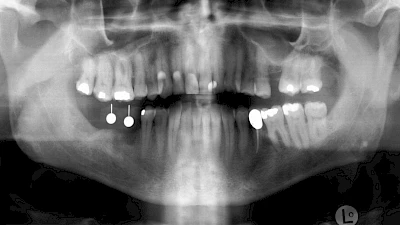

Knochenaufbau und Implantateinsatz

Ist nicht genügend Knochen zur Verankerung eines Implantates vorhanden, kann über einen sogenannten Knochenaufbau die Möglichkeit für das Einbringen eines Implantates geschaffen werden. Dazu kann z. B. Knochen aus der Kieferwinkelregion oder auch aus der Kinnregion entnommen und im Bereich der Fehlstellen aufgetragen werden. Auch künstliches Knochenmaterial kann dabei zum Einsatz kommen.

Im Oberkiefer wird – wenn ein Knochenaufbau notwendig ist – der Knochen in der Regel nicht außen "aufgelegt", sondern es wird der Boden der Kieferhöhle entweder über den Implantat-Bohrkanal durch Verdichtung nach oben gedrückt (interner Sinuslift) oder über eine Fensterung der vorderen knöchernen Kieferhöhlenwand kann Knochen im Bereich des Kieferhöhlenbodens eingebracht (externer Sinuslift).

Knochenaufbau im Unter- und Oberkiefer